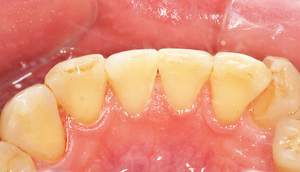

歯石除去

治療前

治療後

| 年齢 | 25歳・男性 |

| 主訴 | 歯石をとりたい・検診 |

| 治療内容 | 各種検査・歯石除去 |

| 治療期間 | 60分 |

| 費用 | 初診料3,000〜4,000円前後 +歯石除去約1,000円 |

| リスク・副作用 | ・処置後に歯がしみることがあります。 ・歯と歯の間に隙間ができるので、息が漏れ発音しにくいと感じることがあります。 ・歯ぐきの炎症が軽減すると歯ぐきが引き締まり、歯が長く見えることがあります。 |

| 担当者所見 | 前歯の裏側にすぐに歯石が溜まってしまいザラザラして気になるとご相談いただいたので適切な歯ブラシの当て方とフロスの通し方をお伝えさせて頂きました。 |